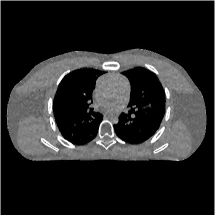

III.C.2. Simulation Framework, Reconstruction Results, and Comparisons

The synthesized low-dose clinical measurements are simulated from regular-dose images at a resolution of mm with a fan-beam CT geometry corresponding to a monoenergetic source at incident photon intensity . The sinograms are of size . The width of each detector column is mm, the source to detector distance is mm, and the source to rotation center distance is mm. We reconstruct images of size with the pixel size being mm mm.

We conducted experiments on one test slice used for parameter tuning (L067-slice 120) and four independent test slices (L109-slice 90, L192-slice90, L333-slice140, L506-slice 100) of the Mayo Clinic data. For PWLS-EP, we ran iterations using relaxed OS-LALM and set regularization parameter . We used the same as the phantom experiments for Algorithm 2. The process of selecting a general set of reconstruction parameters () for the Mayo Clinic test slices is identical to that for the XCAT phantom in Section III.B.2. The selected regularization parameter and the parameters that control the sparsity of the coefficient maps are for ST, , , , , for MARS2, , , , , , , for MARS3, , , , , , , , , , , for MARS5, and , , , , , , , , , , , , , , for MARS7, respectively.

Figs. 8, 9, 10, and 11 show the reconstructions of the four independent slices using the FBP, PWLS-EP, PWLS-ST, PWLS-MARS2, PWLS-MARS3, PWLS-MARS5, and PWLS-MARS7 schemes, respectively. Additional Mayo Clinic experimental results of the parameter tuning case (Fig. 15) are shown in the supplementary document. Table 1 lists the RMSE and SSIM values of reconstructions of the four independent test slices, with the best values bolded. Generally, the five and seven layer models provided the best RMSE and SSIM values. They outperform the single-layer model by HU in RMSE on average. However, the MARS5 and MARS7 models perform similarly. In order to strengthen the benefits of the multi-layer model, Table 2 lists the RMSE of the reconstructions in four different ROIs (shown in the reference of Fig. 11) with seven methods for slice 100 of patient L506. By observing the reconstructed images, we see that although the ST model achieves a cleaner reconstruction result than FBP and PWLS-EP, it still sacrifices some sharpness of the central region and suffers from loss of details. The deeper models have a somewhat more positive effect in terms of maintaining subtle features, which is clearly more essential to clinical diagnosis. Furthermore, as we will discuss later, after considerable parameter tuning, we found that the information contained in residual maps is gradually decreased with the number of layers, eventually vanishing at some layer, which suggests that very deep unsupervised models might not offer significantly better image quality.